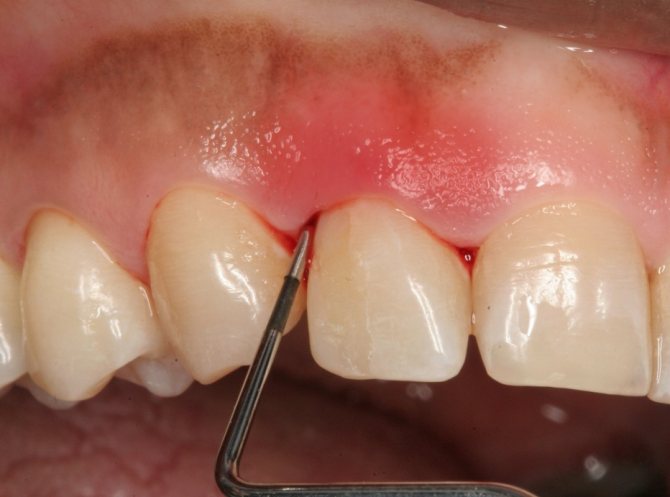

Простуда зубов — очень болезненный симптом, который возникает из-за давления в носовых пазухах. Смотреть галерею

Боль в десне при нажатии

Болезненность десны при нажатии – это симптом воспаления, причиной может быть зуб или окружающие его ткани. Самым простым фактором появления воспаления выступает механическая травма и ожог слизистой оболочки. Тяжелые причины – пародонтит, воспаление верхушки корня, пародонтоз, утрудненное прорезывание зубов. Когда болит зуб при надавливании, это можно связать с кариесом и пульпитом, но в таком случае десна страдают редко, и настоящую причину нужно искать под зубом.